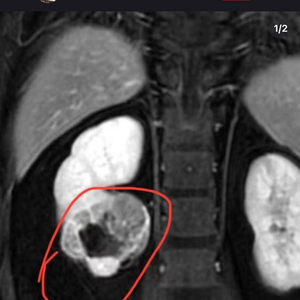

然而,近日一位解压“捏捏”玩具博主

自曝患癌的消息

令公众对于“捏捏”玩具

潜在健康风险的担忧进一步加剧

该博主在社交媒体上发文透露自己罹患癌症,并宣布将暂时停止更新与“捏捏”玩具相关的视频内容。

此举迅速引发了网友的广泛关注和讨论。虽然该博主在文案中并未提及具体的患癌原因,但在评论区,有不少网友怀疑其患癌原因与长时间接触“捏捏”有关。